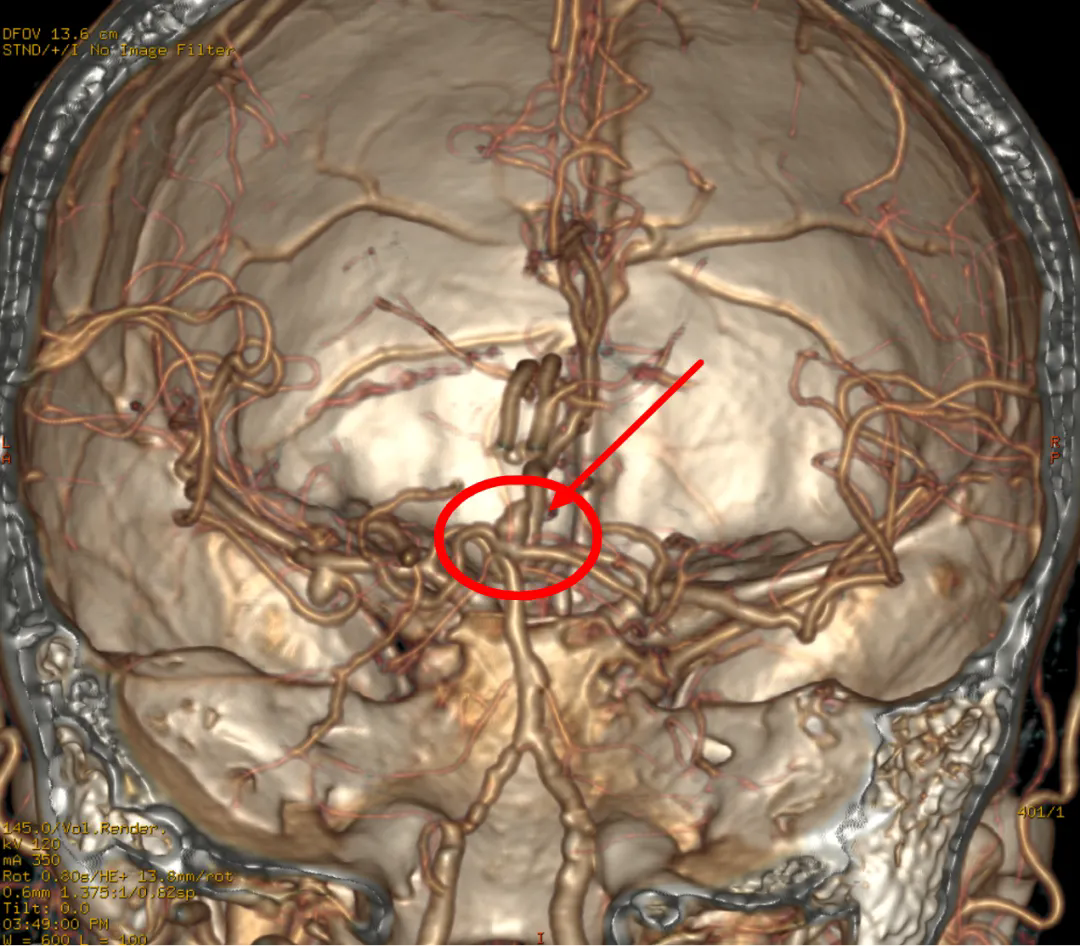

CTA:动脉瘤位置

在各项准备工作完成后,在上级专家的指导下,介入医学科和麻醉科的团队紧密配合,在全身麻醉条件下为患者实施全脑血管造影。经过仔细探索,基底动脉尖动脉瘤被精确定位为责任病。

介入手术中动脉瘤堵塞前后对比

唐汝军介绍说:“这部分靠近脑干和颅神经,手术操作空间很小,技术难度很大。

面对如此艰难的挑战,参与医学的团队以精湛的技术和无畏的勇气,利用支架协助弹簧圈栓塞技术,成功将特殊堵塞材料精确植入动脉瘤腔,完全阻挡血流冲击。